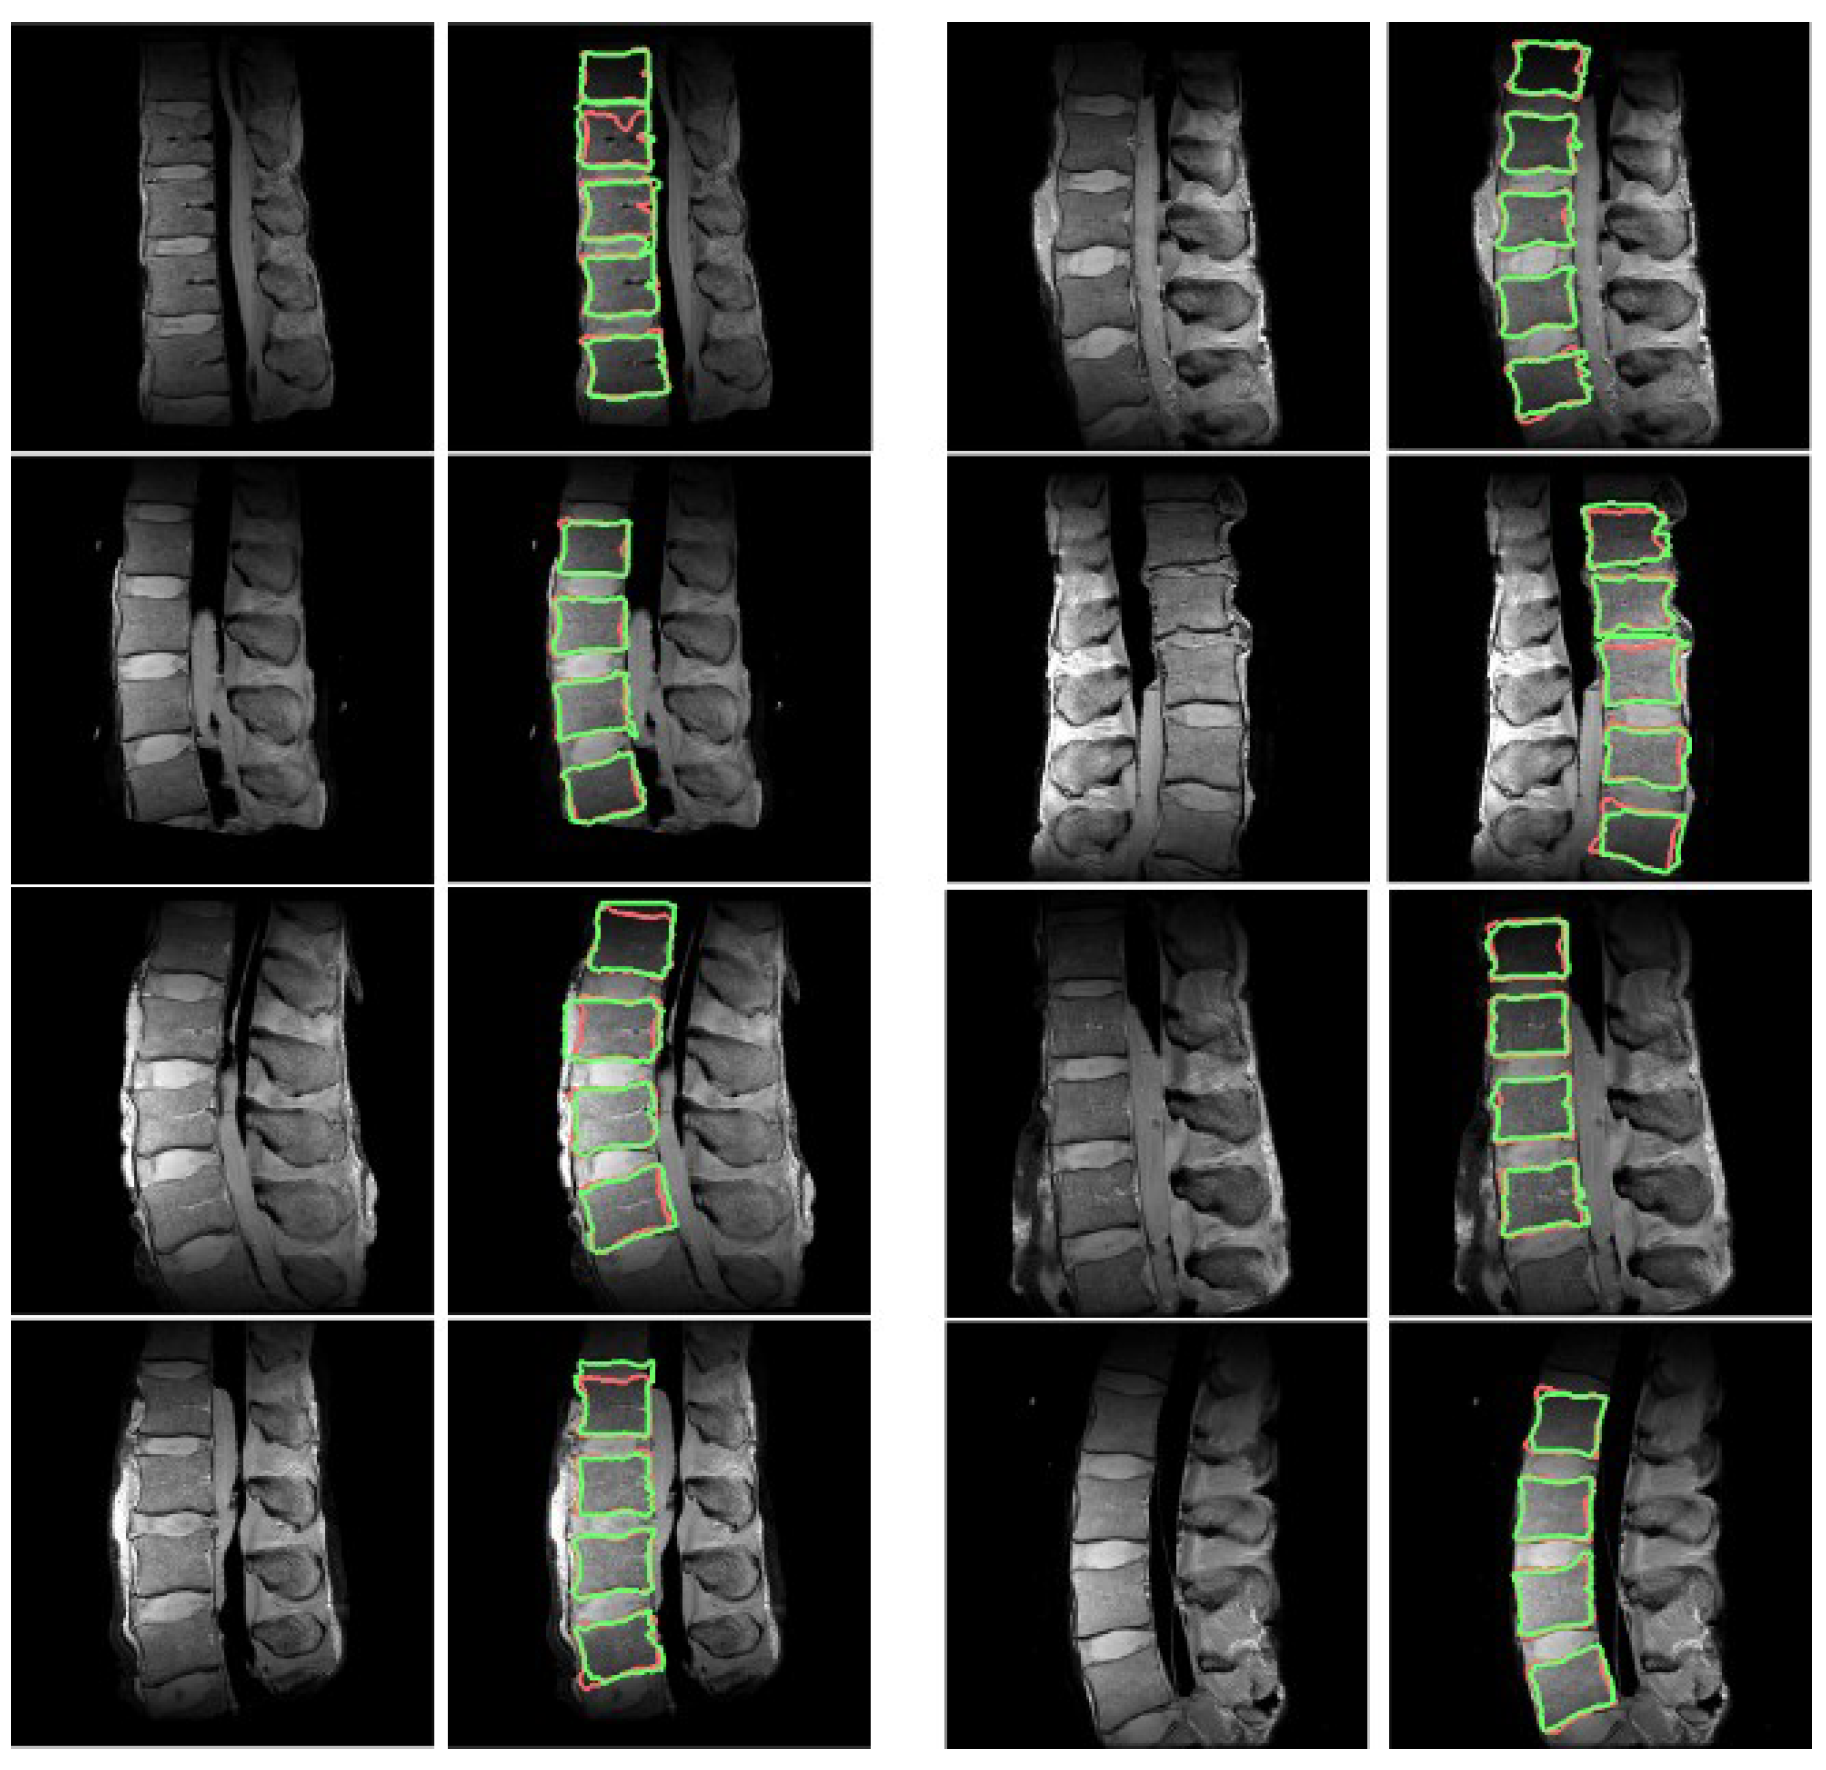

3.1. ROI Detection

3.2. Segmentation Results